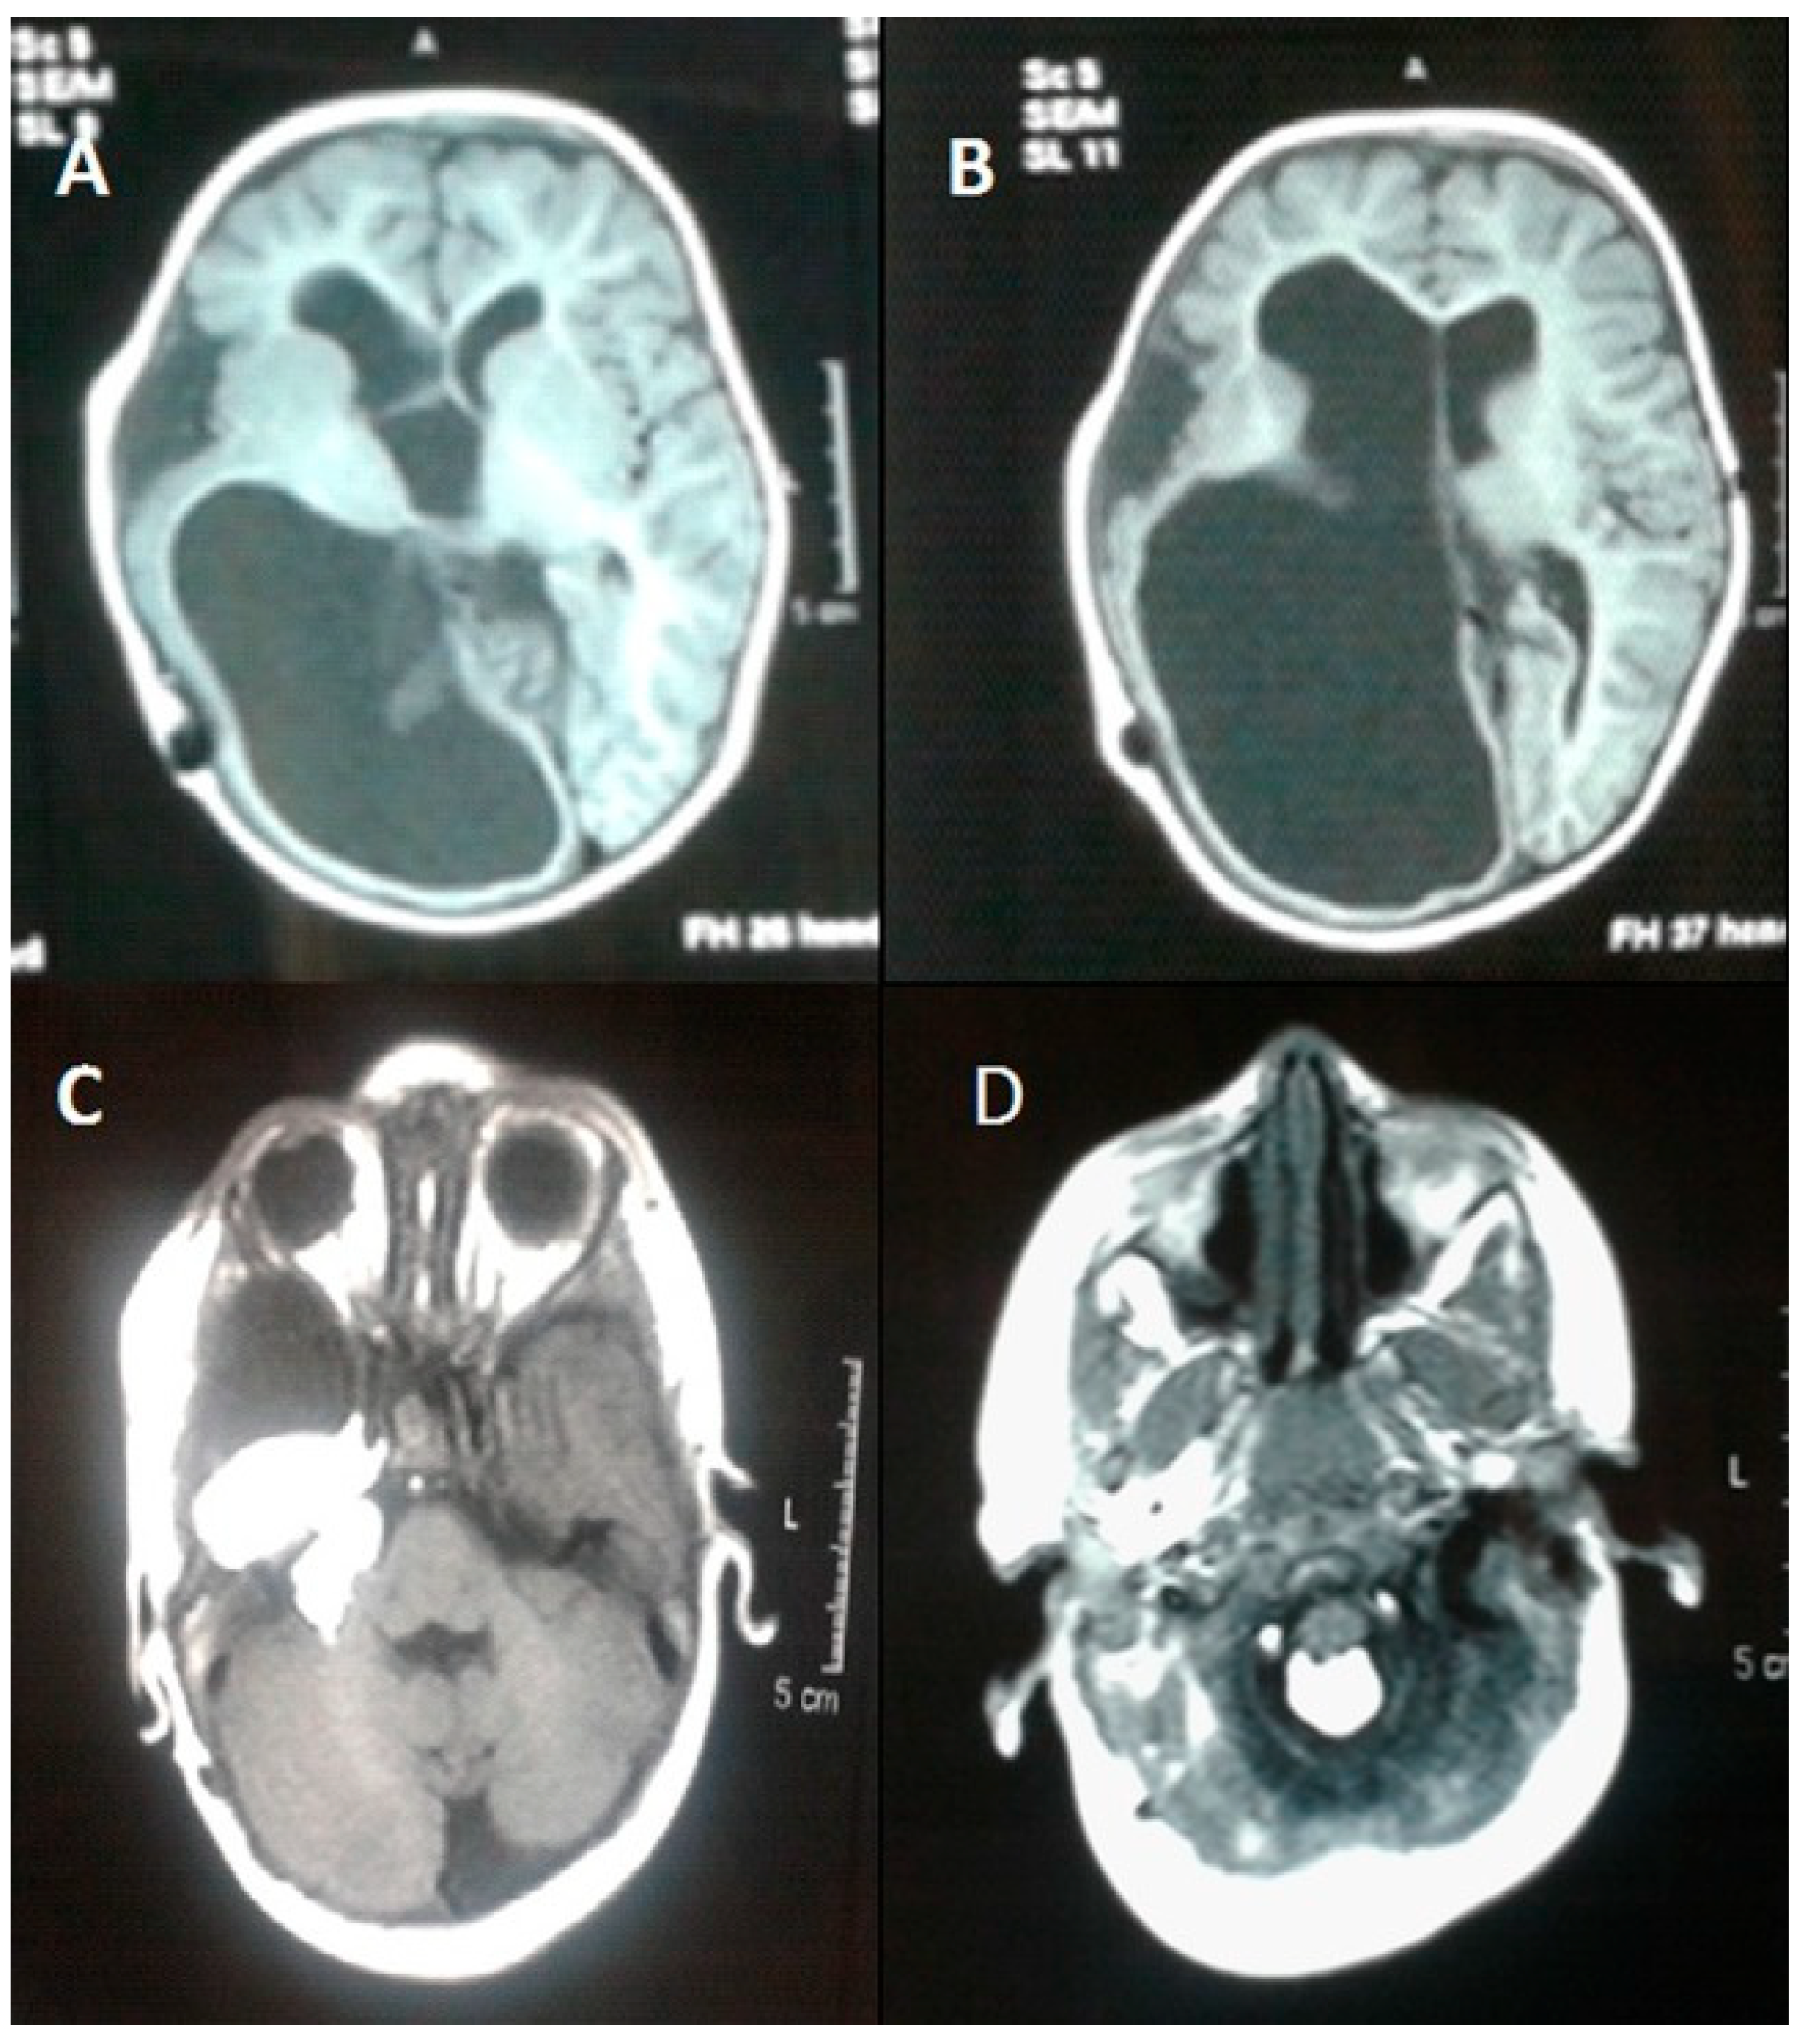

Oculoectodermal Syndrome (OES)

- Siddiqui, S.; Naaz, S.; Ahmad, M.; Khan, Z.A.; Wahab, S.; Rashid, B.A. Encephalocraniocutaneous lipomatosis: A case report with review of literature. Neuroradiol. J. 2017, 30, 578–582. [Google Scholar] [CrossRef] [PubMed]